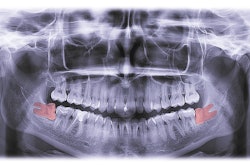

The prophylactic extraction of mandibular third molars is a controversial topic in orthodontics, with significant variability in clinical decision-making. This study aimed to explore the factors influencing such extractions among orthodontists in Israel, they wrote.

Impaction characteristics (35.2%) were the most frequently considered factor for prophylactic extraction followed by mandibular arch crowding (26.1%), with only 4.5% routinely referring patients for extraction.